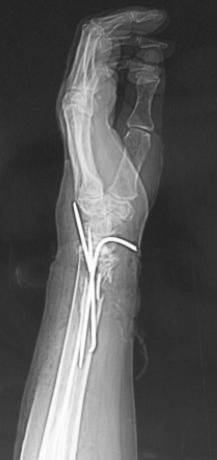

患者王某,老年女性,80岁,主因摔伤致左腕开放性骨折急症于2010年3月入院。查体:患者左侧腕关节处尺骨茎突哆出,掌侧皮肤裂伤,长约6cm,肌腱及皮下组织外露,左腕关节畸形。入院诊断为左侧腕关节开放伤(图1a);左侧桡骨远端骨折;左侧腕关节脱位(图1b)。于入院当日急症臂丛麻醉下行左腕伤口清创缝合术,左侧尺腕关节复位内固定术,左侧桡骨远端骨折复位内固定术(图2)。手术过程顺利,术后患者恢复良好,约术后5周拔除左侧腕关节固定克氏针,后患者自动出院。出院后1日患者因突发喘憋,进行性加重再次就诊于我院,血气分析示PO2 36.3mmHg,PCO2 30.4mmHg,D-二聚体4000ng/ml,胸CT示左下肺大片高密度影,肺通气灌注扫描显像提示双肺多发节段灌注缺损。入院诊断为:I型呼吸衰竭;肺栓塞;冠心病;高血压病3级;糖尿病2型;左桡骨远端骨折。给予速碧林 4100IU/d经验性抗凝治疗。第2日患者喘憋症状明显缓解,自诉无呼吸困难,动脉氧分压升至141mmHg(鼻导管吸氧5L/分)。应用速碧林3日后加用华法令5mg /d,间断复查KPTT及INR,华法令与速碧林重叠应用5日后,患者PT延长至18.9s,即停用速碧林,单独应用华法令,1周后患者好转出院。

图2 患者术后X线片。